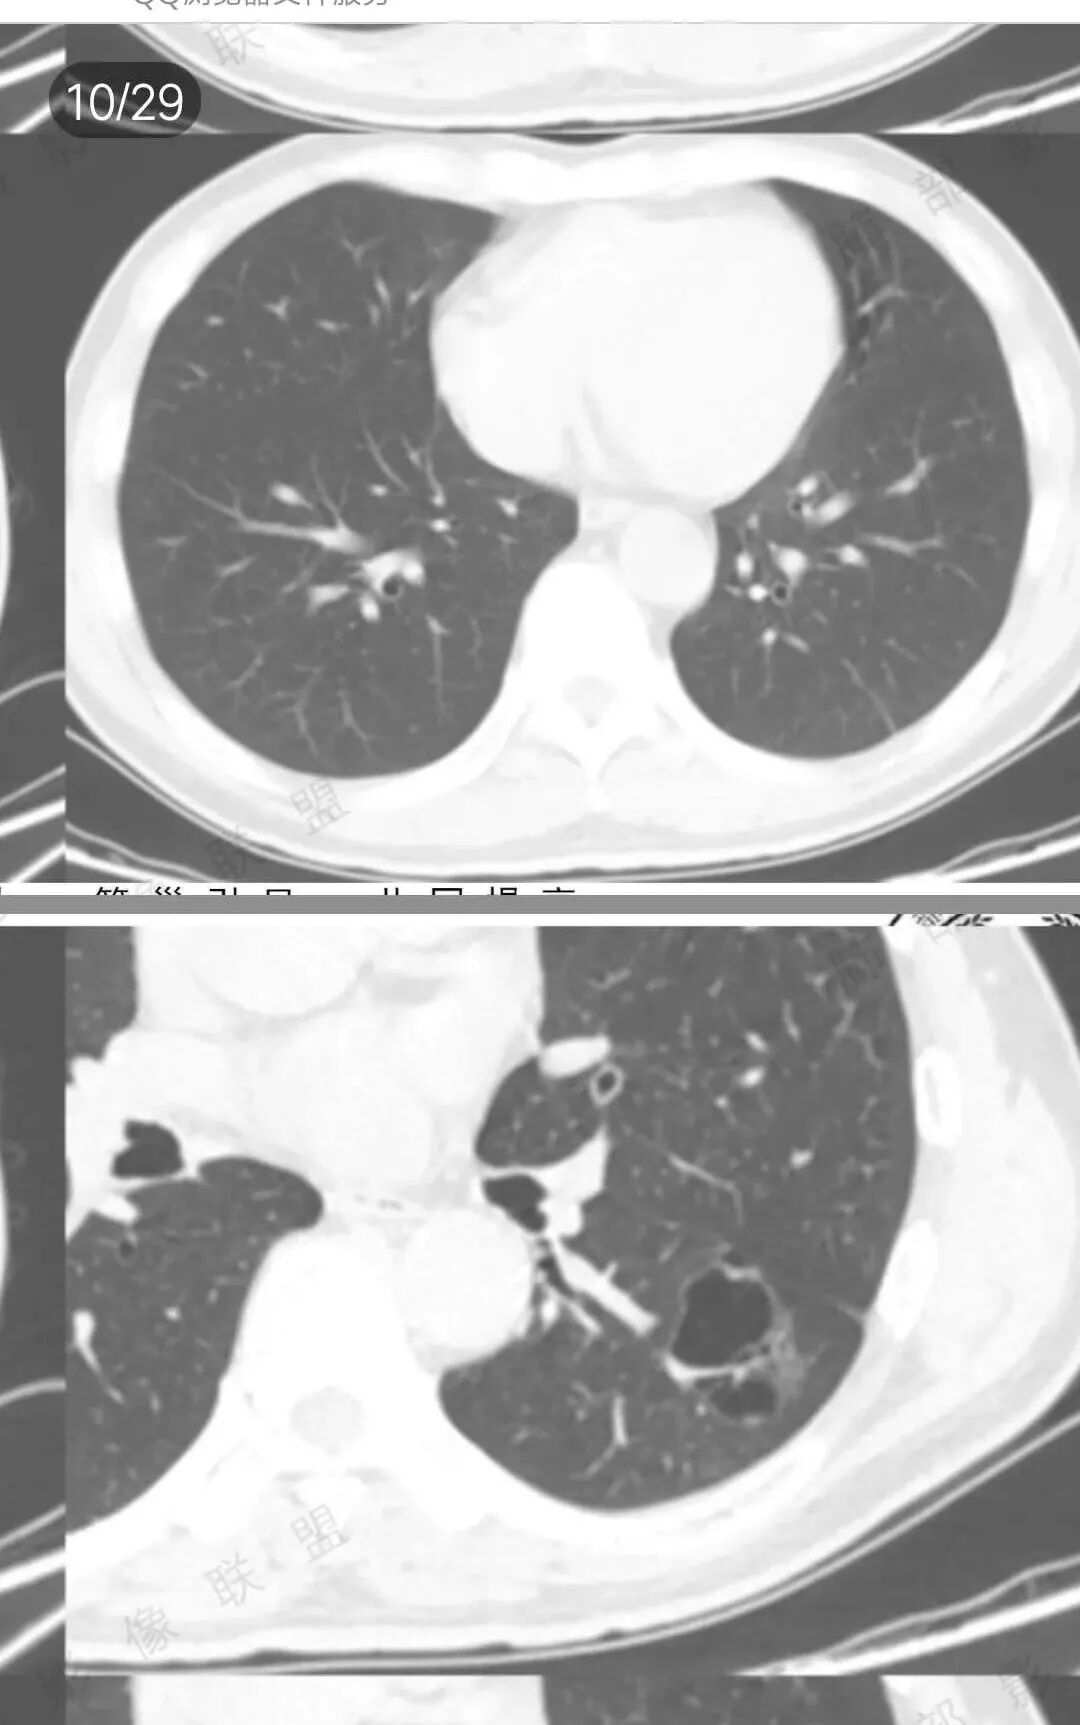

左肺下叶空腔,分隔状,壁厚薄不均,支气管截断,部分周围可见磨玻璃影,胸膜牵拉,左肺上叶多发结节,部分可见钙化,考虑1左肺下叶囊腔型腺癌。2左肺上叶结核。

男51,体检发现肺部阴影,左肺下叶见多发薄壁囊腔影,可见结节,囊腔内见分隔,轻度胸膜牵拉,病灶周围少许磨玻璃影,常规考虑囊腔型腺癌,肿瘤标志物不高,除外结核。

中年男性,体检发现,吸烟史,但肺气肿背景不明显。左肺下叶囊腔病变,有一定张力,分隔明显,似有多个囊腔融合感,部分边缘见少许磨玻璃影,有支气管截断,首选囊腔型肺癌,某些先天病变(囊腺瘤样畸形等)也要考虑。

左肺上叶多发小结节影,部分钙化,考虑结核。左肺下叶多个囊状影,腔内见血管影,间隔稍粗大,考虑囊腔型肺癌,

老年,51岁男性病人,左上肺斑点,小结节状阴影,可见钙化,陈旧性肺结核改变,患者有长期的吸烟病史。左肺下叶背段多个囊腔肿块影,整体呈团块状类圆型,无明显壁结节,整体病灶张力较大,具备一定的膨胀感 ,支气管拉直并有突然截断改变,考虑囊腔型鳞癌。鉴别诊断:结核性病变,局限性囊性支气管扩张

孤立性的多囊型病变伴分隔。ccam,肺隔离征,囊性肺癌,闭锁。。这是大家上面写的。看看怎么排除。血管看到肺动脉进入供血,没有感染液平,肺隔离不符合。没有代偿肺气肿,支气管没有闭锁,闭锁不考虑。那锁定ccam和肺癌。我们临床也常见是支气管畸形所致的囊。

我们看哪些内容,第1.周围有没有毛玻璃2.分隔有无粗细不均或结节,壁有无厚薄不均有无壁结节3.支气管,4.随访。

男性,体检发现左肺阴影。影像表现:左上肺多发结节伴纤维条索影,部分钙化,左下肺囊腔样改变,内有分隔,部分分隔边缘见实性成分及GGO样改变,支气管从旁边经过,或受压,无明确进入依据。初步诊断:1、左上肺结核。2、左下肺囊腔型腺癌,诊断依据:分隔样囊腔,部分分隔有实变,边缘有GGO改变,鉴别诊断:1、囊腺瘤样畸形,分隔样囊腔要考虑,但部分分隔实变,部分伴GGO样改变成疑,最大的疑问是年龄51岁,体检发现,抽烟、饮酒30年,却无发病,可能性太小。2、囊腔性转移,单发分隔样囊腔转移少见,且需要病史支持。3、囊性淋巴瘤,一般以单发囊腔多见,分隔样囊腔型淋巴瘤罕见。4、感染,无相关临床症状及辅检支持,基本排除。

@傅昌瑜—贺州市人民医院—呼内 这个层面的GGO还是比较确定的。

@傅昌瑜—贺州市人民医院—呼内 里面的血管进一步支持恶性。但不鉴别腺癌和鳞癌,主要鉴别的,还是多囊,张力较高,囊壁较薄(实变区除外),加GGO。

囊腔型肺癌

囊腔型肺癌是一种特殊形态的肺癌,病灶边缘或中央存在一个或多个含气的囊腔,其囊腔直径大于5mm(小于5mm的为空泡)、囊壁厚度小于4mm,当影像上难以判断空洞或空腔时,可以笼统定义位于囊腔样病变。囊腔肺癌以腺癌多见,鳞癌少见,早期表现不典型时容易误诊或不被重视。

囊腔型肺癌的诊断要点

1.囊壁是否规则,内壁是否光整。

2.囊壁是否存在不规则增厚或伴有壁结节。这有时需要薄层冠矢状位观察。应留意壁结节及增厚囊壁有无异常强化。

3.囊腔内结构:囊内如果有分隔、支气管及血管穿行应该考虑空腔,而非空洞,这种需要高度怀疑恶性

4.囊腔周围是否有清楚的磨玻璃影,如果有强烈提示腺癌

5.病灶是否有分叶、毛刺、支气管截断、血管集束征、胸膜凹陷征等周围型肺癌的影像征象。应留意同侧肺门及纵隔有无增大淋巴结。